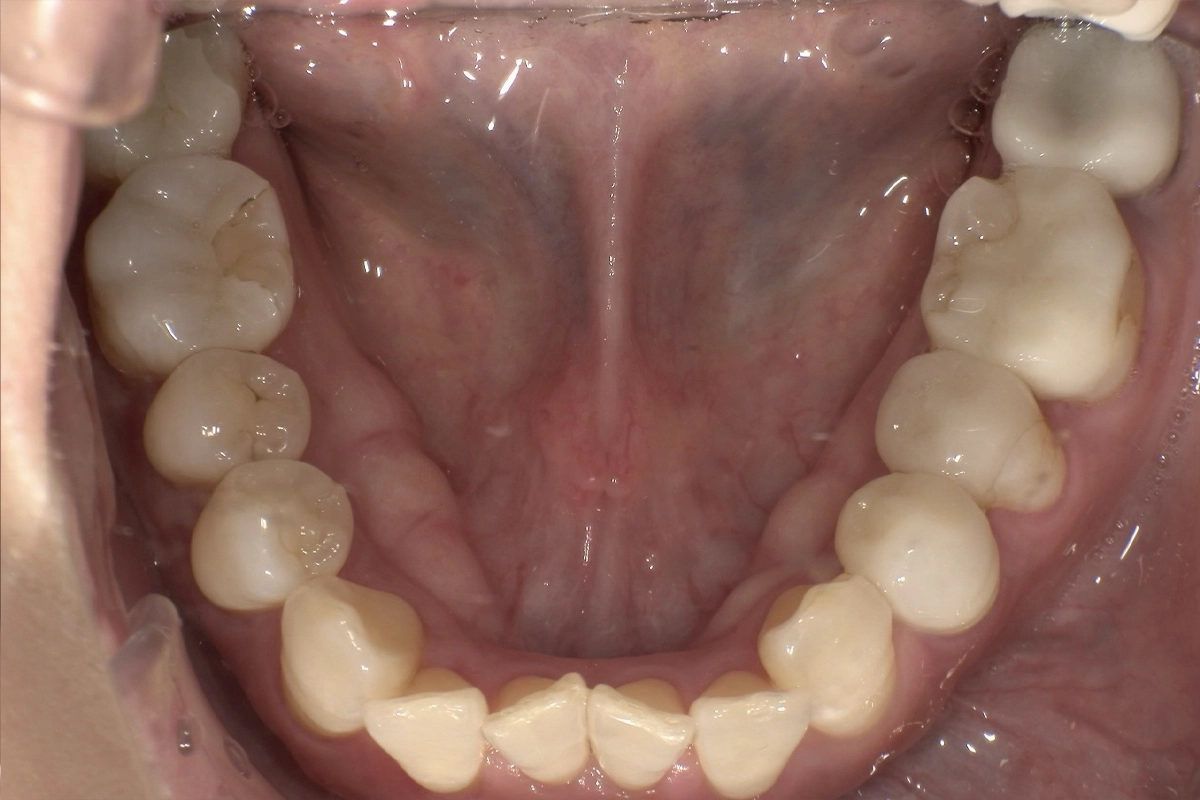

特に下の前歯は歯同士が重なり合い、一部の歯が前後にずれて不規則に並んでいる状態でした。

歯が重なった部分には歯ブラシの毛先が届きにくく、実際に歯と歯の間に歯石の沈着も確認されました。

歯が重なり合っている部分は、毎日の歯みがきだけでは十分に汚れを落としきれません。

治療前の写真では、下の前歯の歯頸部(歯と歯茎の境目)に歯石の付着が見られ、清掃が行き届いていないことがうかがえます。

歯の重なりが解消されたことで、歯ブラシやフロスが隅々まで届きやすくなりました。

治療前に見られた歯石の沈着しやすい環境が改善され、虫歯や歯周病の予防がしやすい状態になっています。